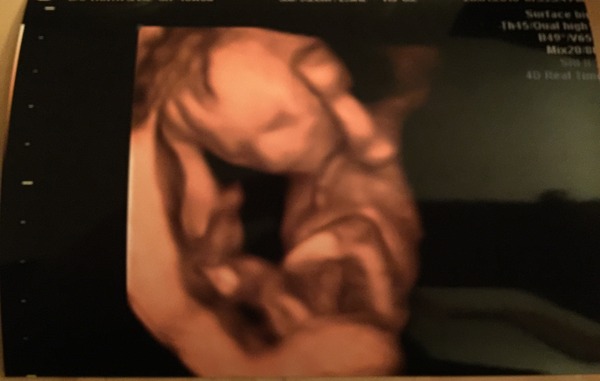

On Thursday I had a 2d/3D scan - IM HAVING A GIRL!!!!Grin Scan was amazing.... Saw her waving her, opening her mouth. I'll attach a pictureSmile